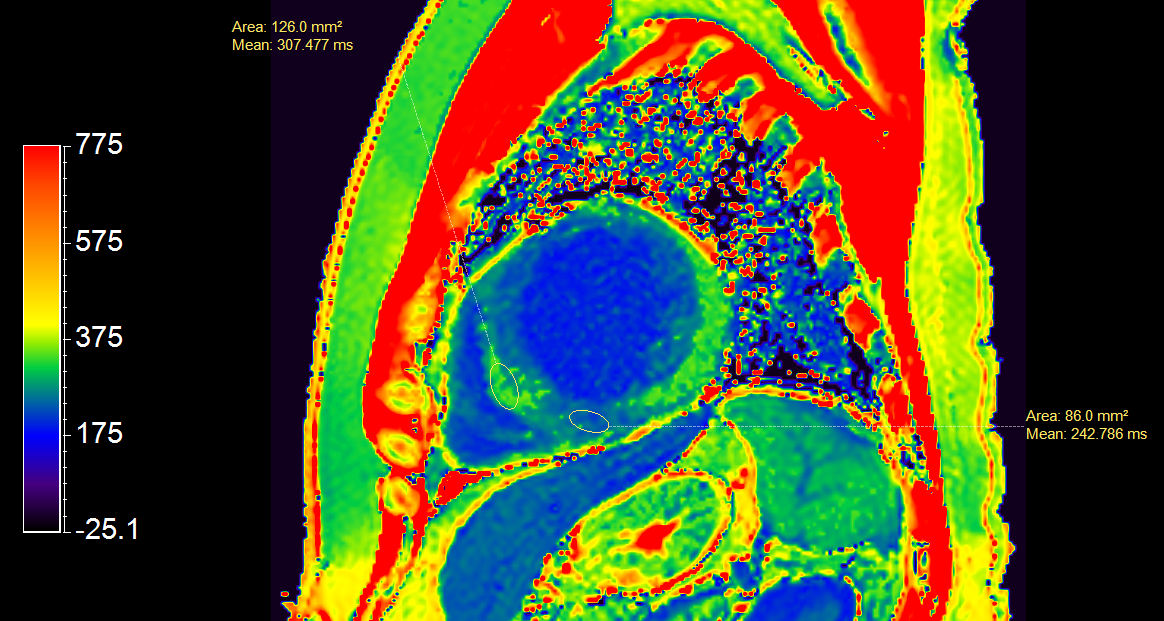

Short axis view T2 Map

Short axis view (T2 Mapping on ISP 12)

4 chamber view T2 Map

4 chamber view (T2 Mapping on ISP 12)